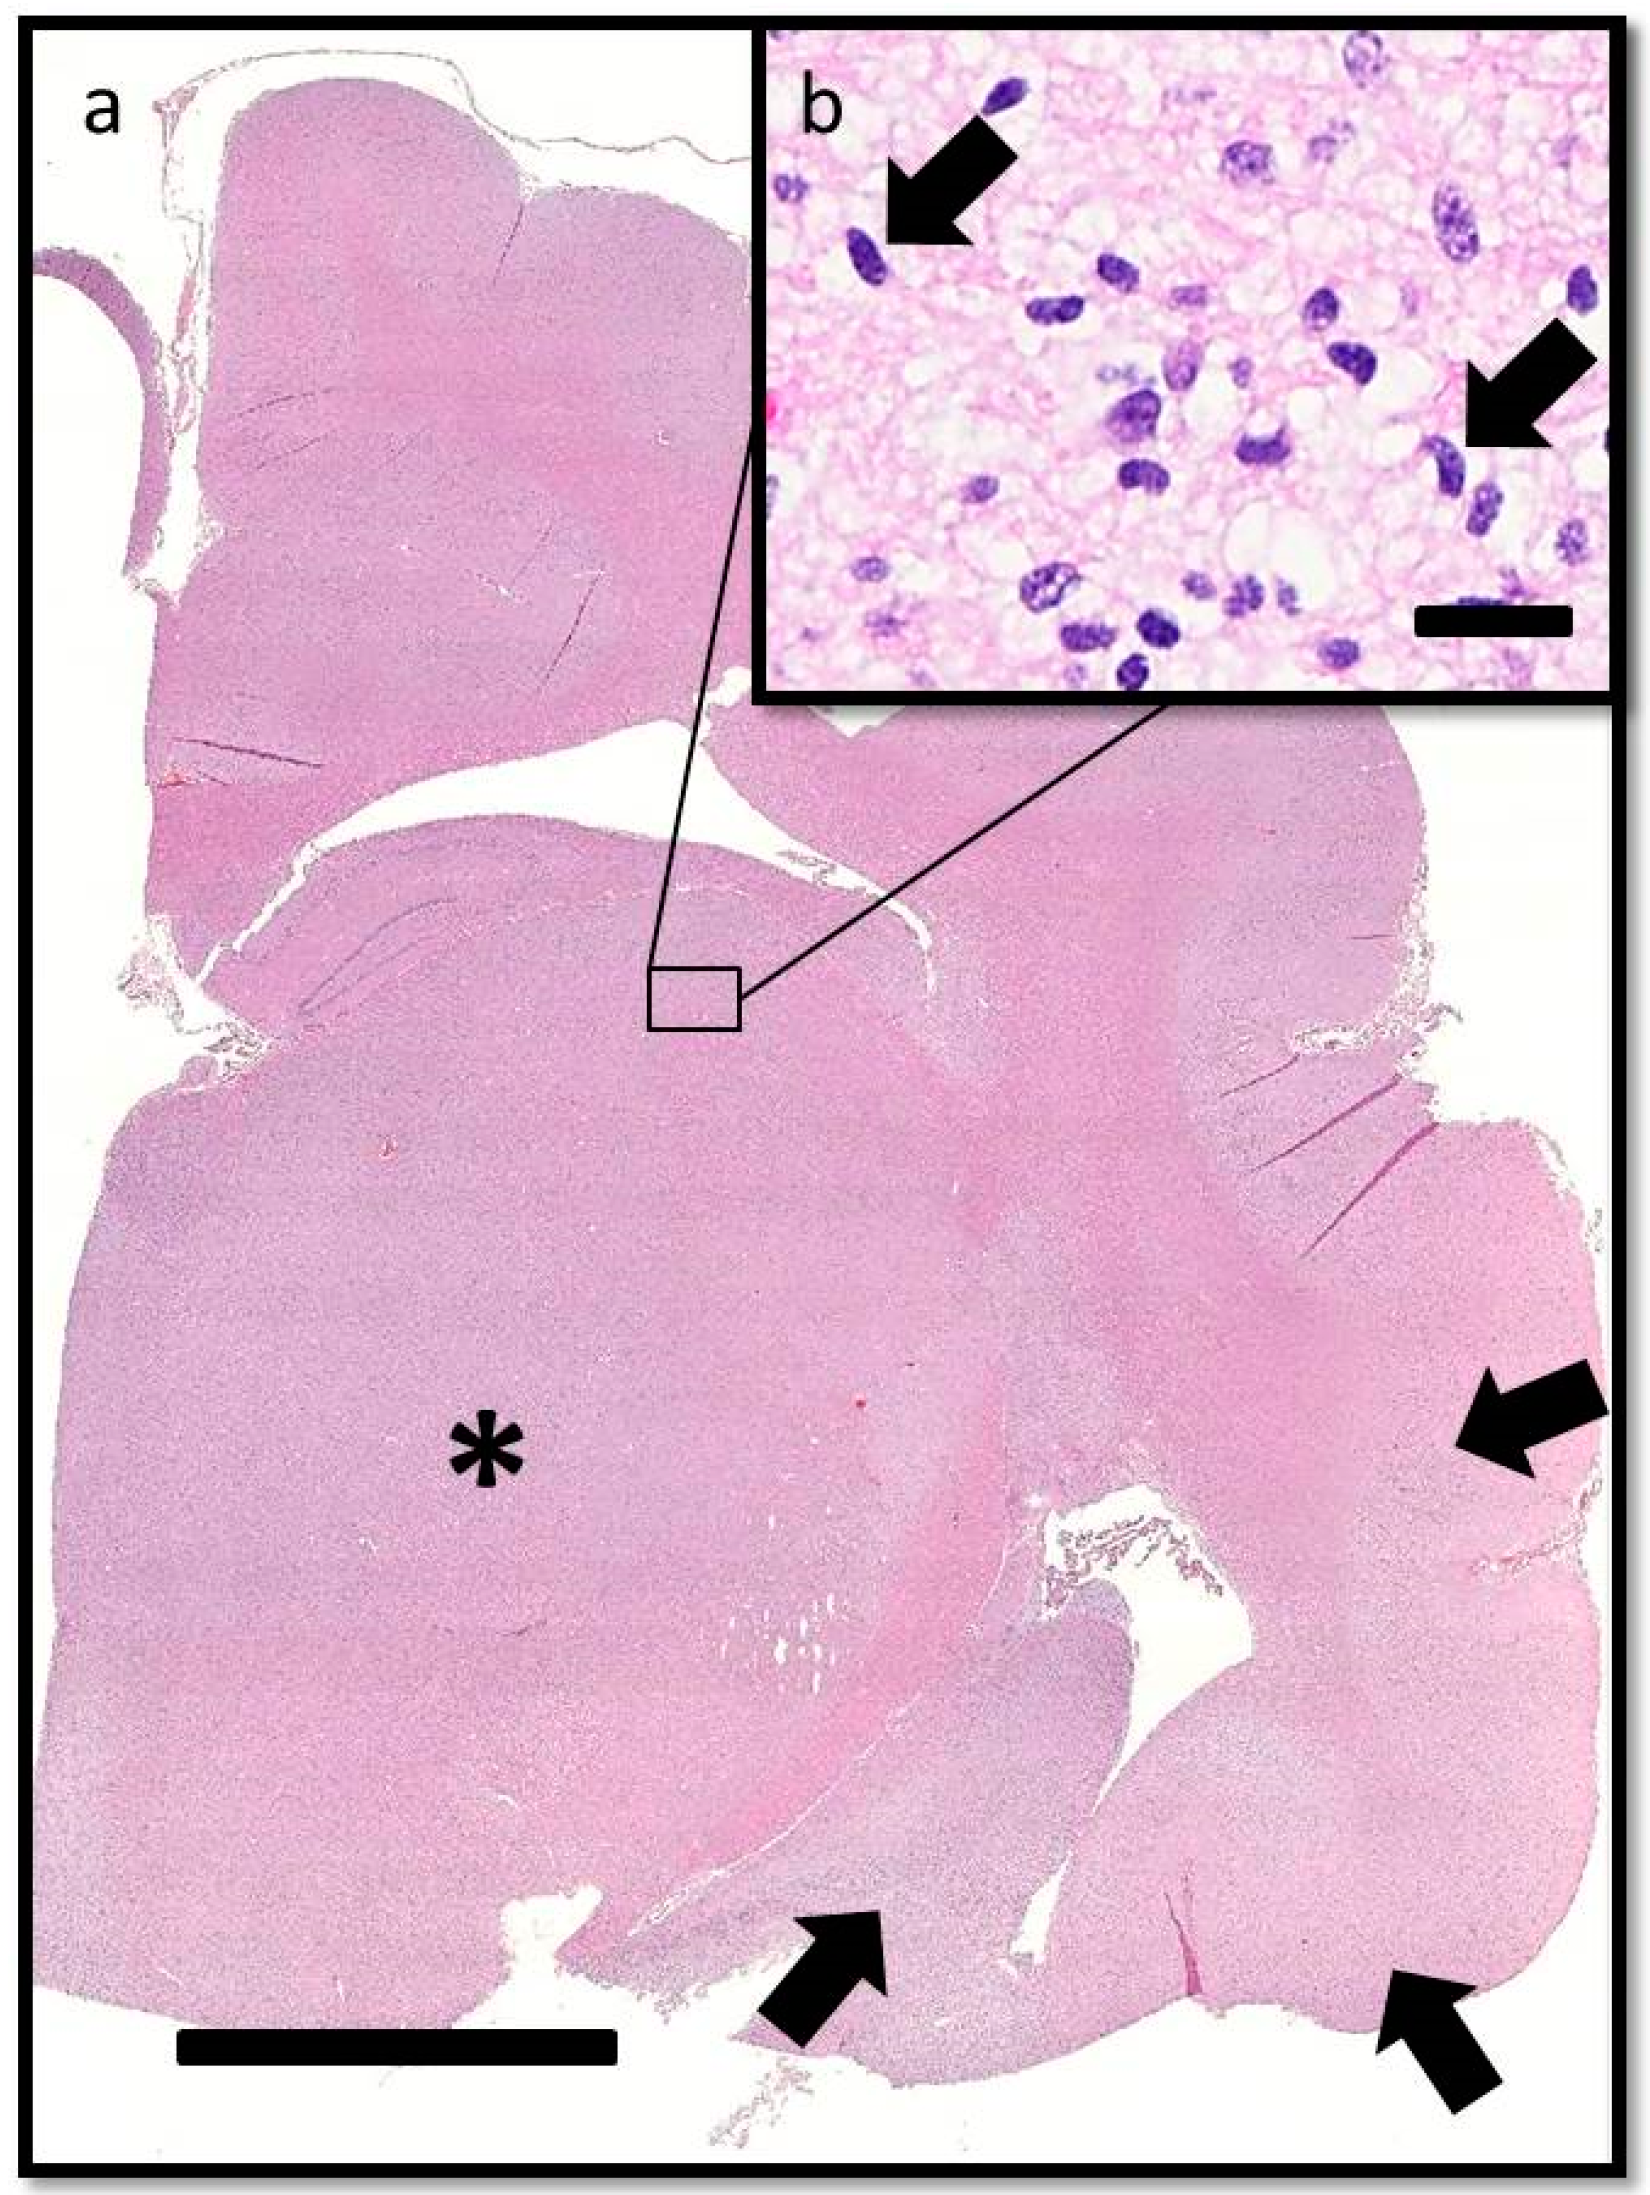

On post-mortem examination, changes were confined to the central nervous system. Gross examination of the brain confirmed compression of the caudal cerebellum, caudal transtentorial herniation of the midbrain, and herniation of the cerebellar vermis. There was mild to moderate flattening of the straight, suprasylvian, ectosylvian, sylvian, dentate, and occipital gyri with narrowing of the rostral rhinal, lateral rhinal, suprasylvian, and ectosylvian sulci. On the cut surface, the corpus striatum, thalamus, and hippocampus were soft and had loss of detail, but lacked a grossly discernible mass (Figure 3). The spinal cord was unremarkable. Mild spondylosis deformans was present at L3-L4; however, there was no gross evidence of diskospondylitis.

Figure 3. Transverse section of formalin-fixed brain at the level of the septal nuclei. There is mild to moderate flattening of the suprasylvian, ectosylvian, and sylvian gyri (arrows) with narrowing of the associated sulci. The ventral aspects of the corpus striatum (astrices) have bilateral but asymmetrical loss of detail. Bar = 1 cm.